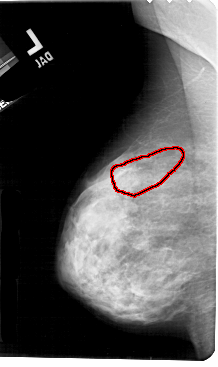

A_1699_1.LEFT_MLO

LEFT_MLO LINES 5491 PIXELS_PER_LINE 3256 BITS_PER_PIXEL 12 RESOLUTION 43.5 OVERLAY

FILE: A_1699_1.LEFT_MLO.OVERLAY

TOTAL_ABNORMALITIES 1

ABNORMALITY 1

LESION_TYPE CALCIFICATION TYPE PLEOMORPHIC DISTRIBUTION SEGMENTAL

ASSESSMENT 4

SUBTLETY 3

PATHOLOGY MALIGNANT

TOTAL_OUTLINES 1

BOUNDARY